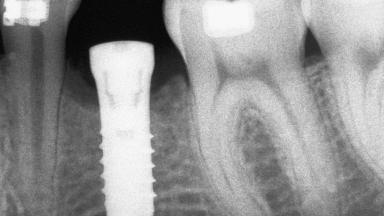

An 18-year-old man was referred for implant therapy in the posterior mandible to the Department of Oral Surgery and Stomatology (University of Bern, Switzerland). He was healthy and did not smoke. Tooth 35 was congenitally missing, involving a single-tooth edentulous space that offered an adequate mesiodistal dimension for implant placement but exhibited a typical pattern of buccal flattening. A panoramic radiograph was obtained, which revealed a sufficient vertical bone height above the mandibular canal and a normal bone structure in the edentulous area.

Bone Volume Deficient horizontally, requiring prior grafting